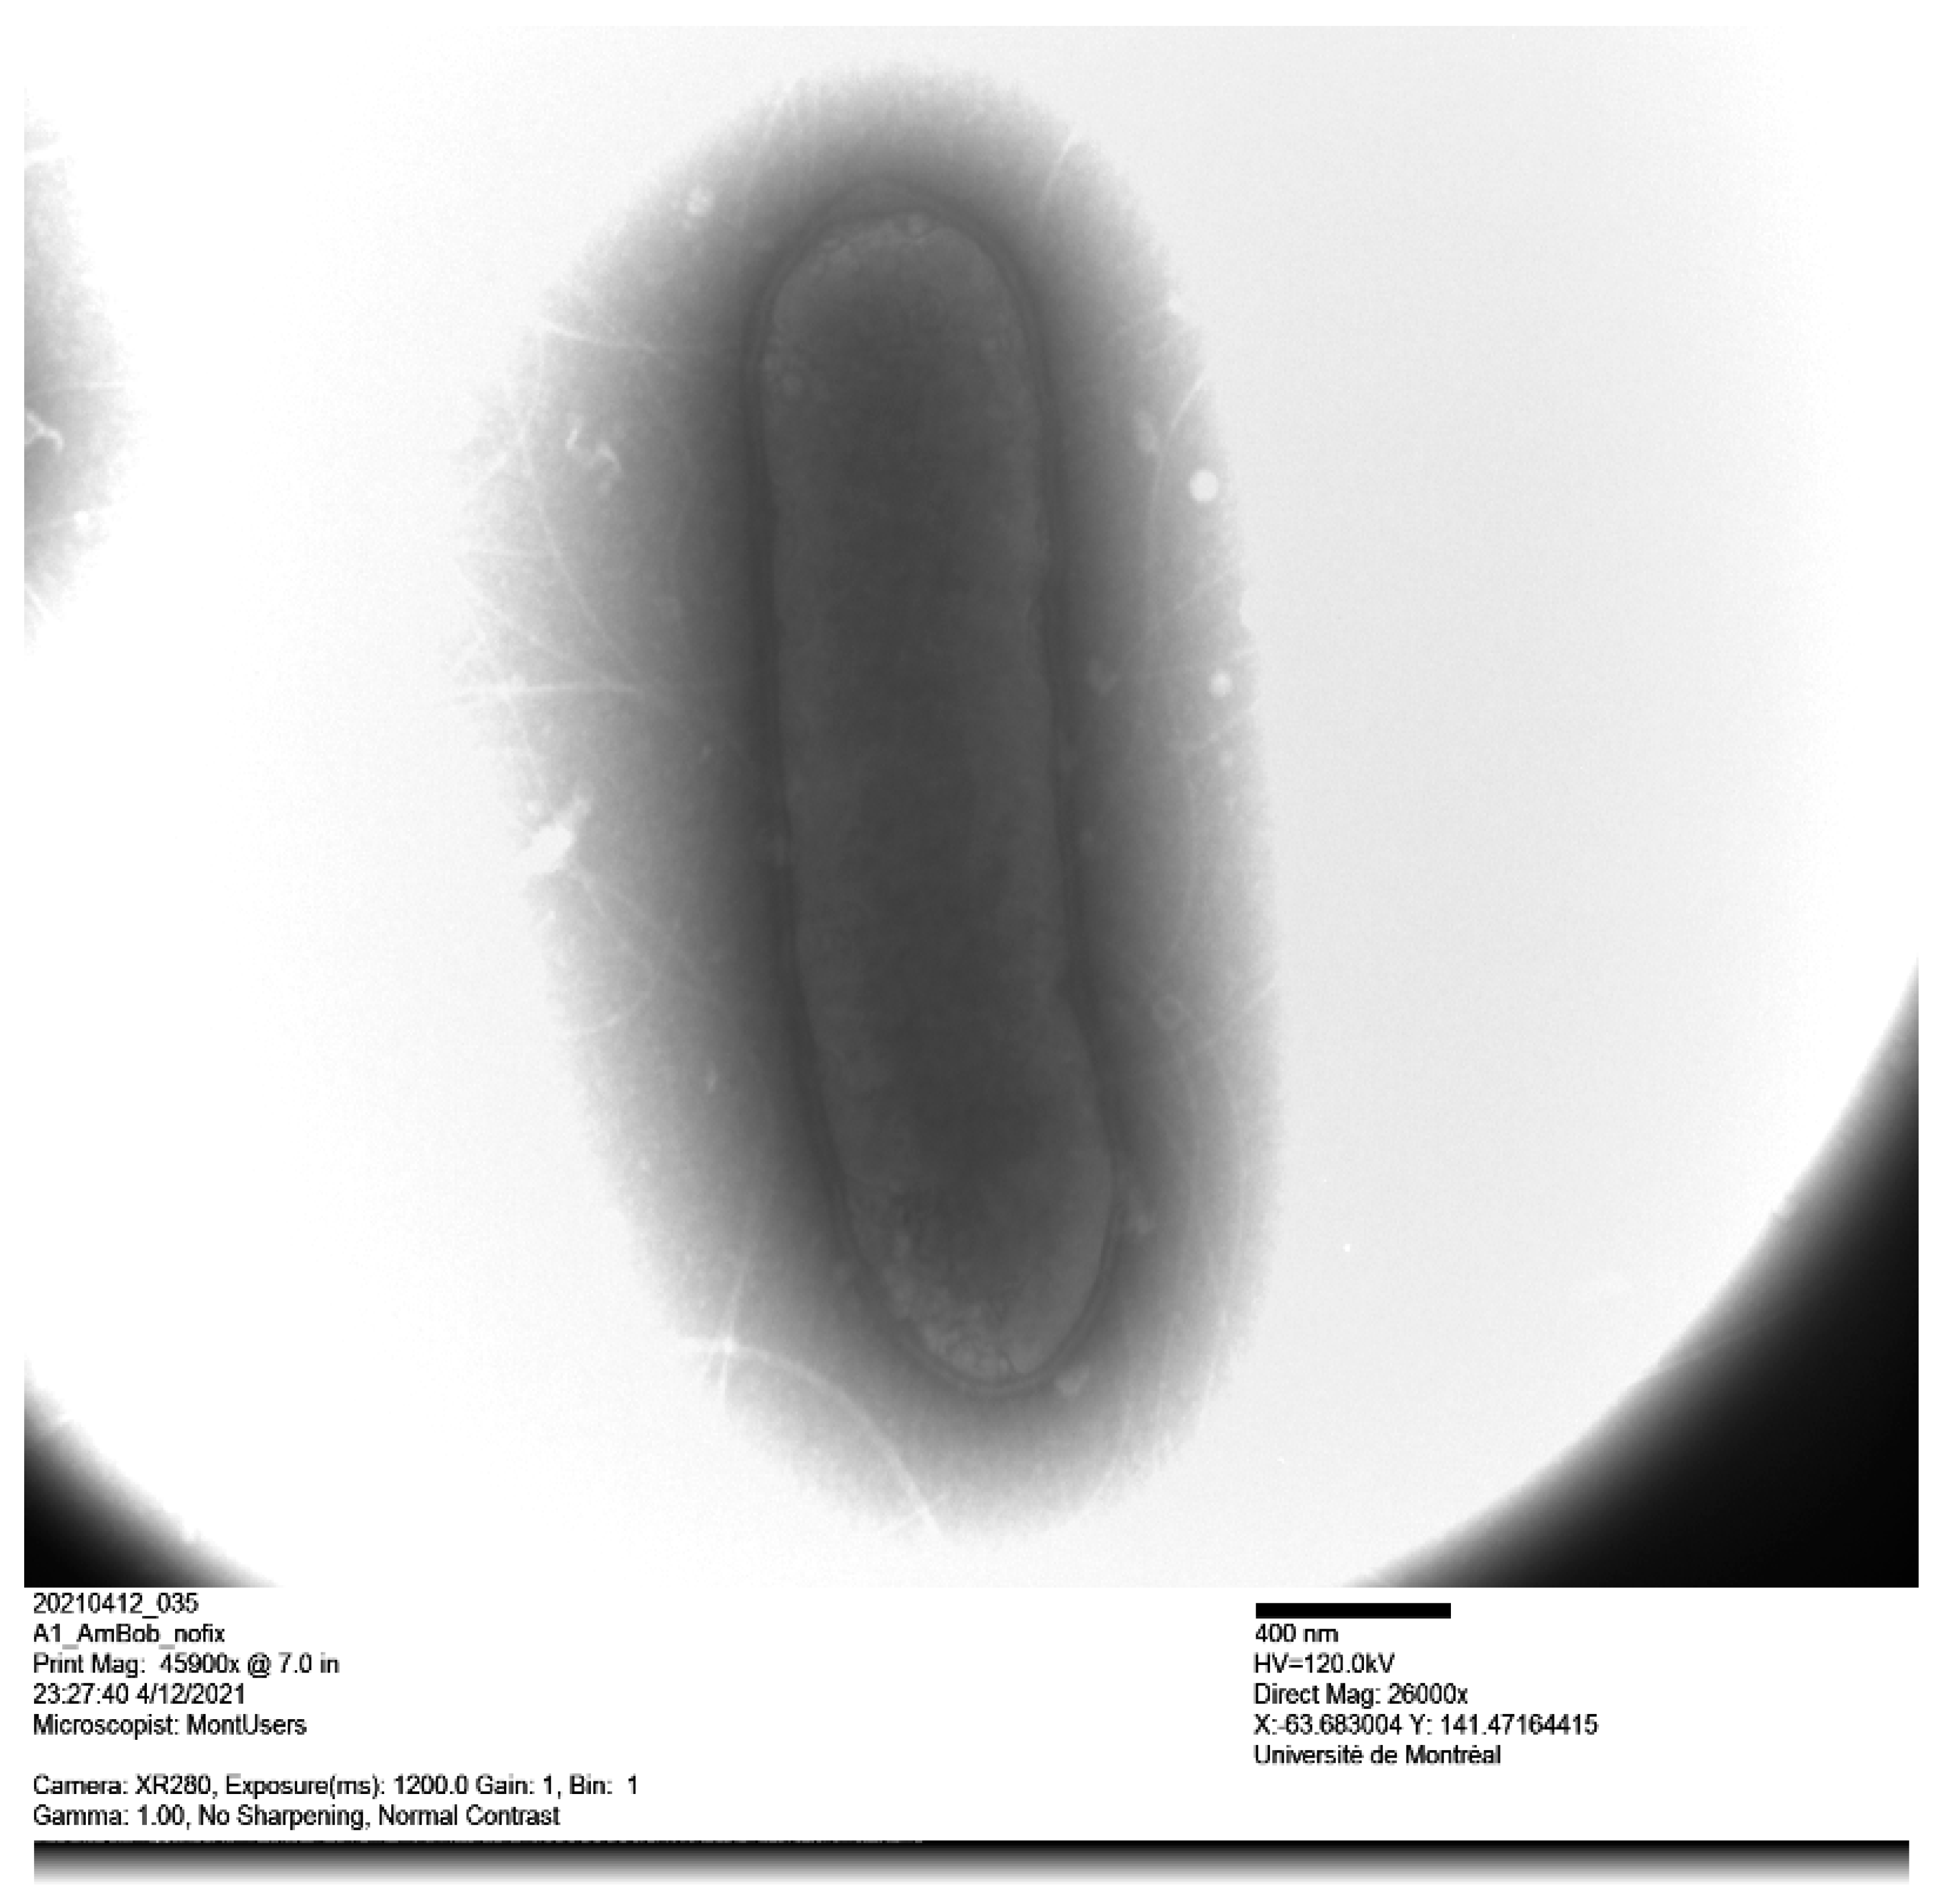

3.2. Phenotypic Features